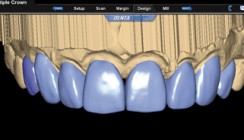

Der Einsatz digitaler Volumentomografie eröffnet ohne Frage ein breites Spektrum an diagnostischen Möglichkeiten (Abb. 1 und 2). Um hierbei jedoch betriebswirtschaftlich sinnvoll agieren zu können, müssen einige wichtige Aspekte berücksichtigt und im täglichen Umgang mit DVTs entsprechend umgesetzt werden. So stellen neben dem großen Investitionsvolumen insbesondere der Datenschutz sowie die Langzeitarchivierung den Praktiker vor große Probleme.